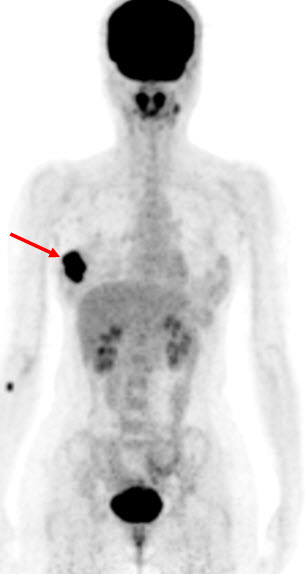

Hình 4 (a, b) cho thấy giá trị của PET/CT trong đánh giá giai đoạn của ung thư vú. Bệnh nhân Nguyễn Th. T. Tr., nữ, 63 tuổi, chẩn đoán là ung thư vú. Kết quả PET/CT toàn thân cho thấy nhiều tổn thương di căn hạch cổ, hạch trung thất, di căn 2 phổi, gan, xương tăng hấp thu FDG.

Hình 4a. Hình PET toàn thân thấy nhiều tổn thương hạch cổ, hạch trung thất (mũi tên vàng), phổi (mũi tên đỏ), gan (mũi tên tím) và xương (mũi tên xanh) tăng hấp thu FDG.

Hình 4b. Hình PET/CT ở mặt phẳng cắt ngang thấy tổn thương di căn phổi (mũi tên đỏ) và di căn gan (mũi tên da cam).